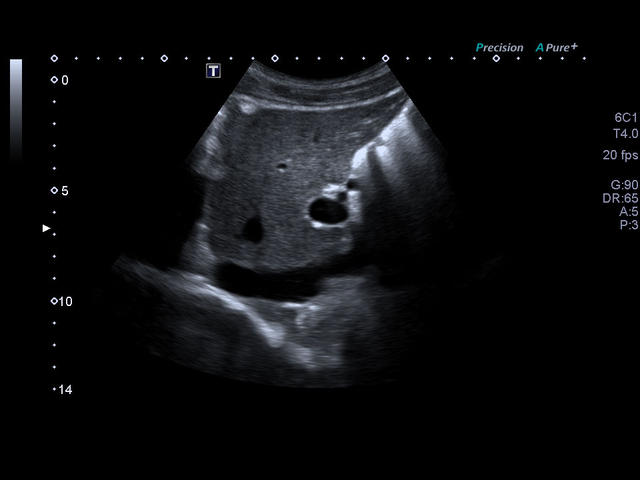

- Абдоминальные исследования

- Гинекология

- Акушерство

- Объемная визуализация.

- Максимальная глубина сканирования: 40 см